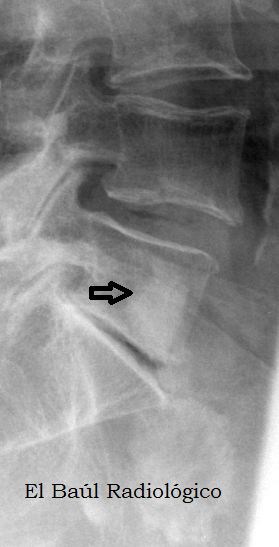

FIGURA 2) El islote óseo también se aprecia en una radiografía convencional de la columna.

(The bone island is also seen in a conventional radiography of the spine).

FIGURA 4) El islote óseo se aprecia en una radiografía convencional de la columna lumbar.